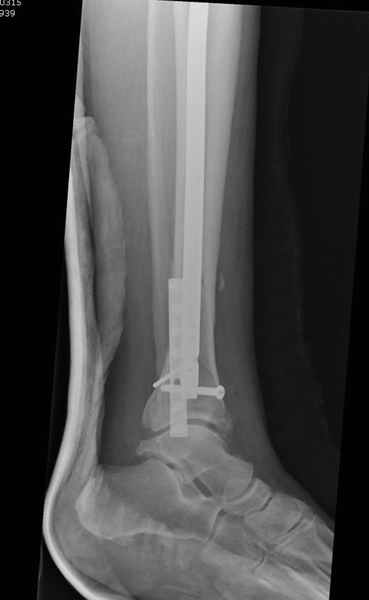

У меня молодой врач на линии, снимки отправил через эл. почту,

спрашивает что делать с больным который поступил недавно, фермер 55 лет падение при пьяной драке в баре, года два назад перенес операцию на лодыжке, на снимках и КТ перелом без вовлечения сустава,

Повреждение такой локализации, на которой применимы и аппарат (классический Илизарова или гибридный), пластина, особенно Locked Plate, и гвоздь с блокированием. В нашей клинике был бы выполнен закрытый интрамедуллярный остеосинтез. Желательно использовать гвоздь с возможностью провести более чем 2 обычных фронтальных винта в дистальном отломке.

Здесь мы использовали новый Synthes Nail с дополнительными дырками, в проксимальной части 4: по две косых и поперечные (один стандартный а другой динамический), в дистальной части две поперечные, прямая и косая. Вес больного более 120 кг, нагрузку начнем через месяц.

Получилось красиво, поздравляю. Вверху можно было ограничиться одним винтом во фронтальное статическое отверстие, зачем два 45-градусных?

При такий спирали задний край tibia может быть сломан - нет ли этого в данном случае? На всякий случай можно было ввести 1-2 винта 4,5 мм спереди назад мимо гвоздя. Хотя самый дистальный блокирующий винт, возможно, зацепил этот отломок. А какой тут диаметр гвоздя и locking винтов?